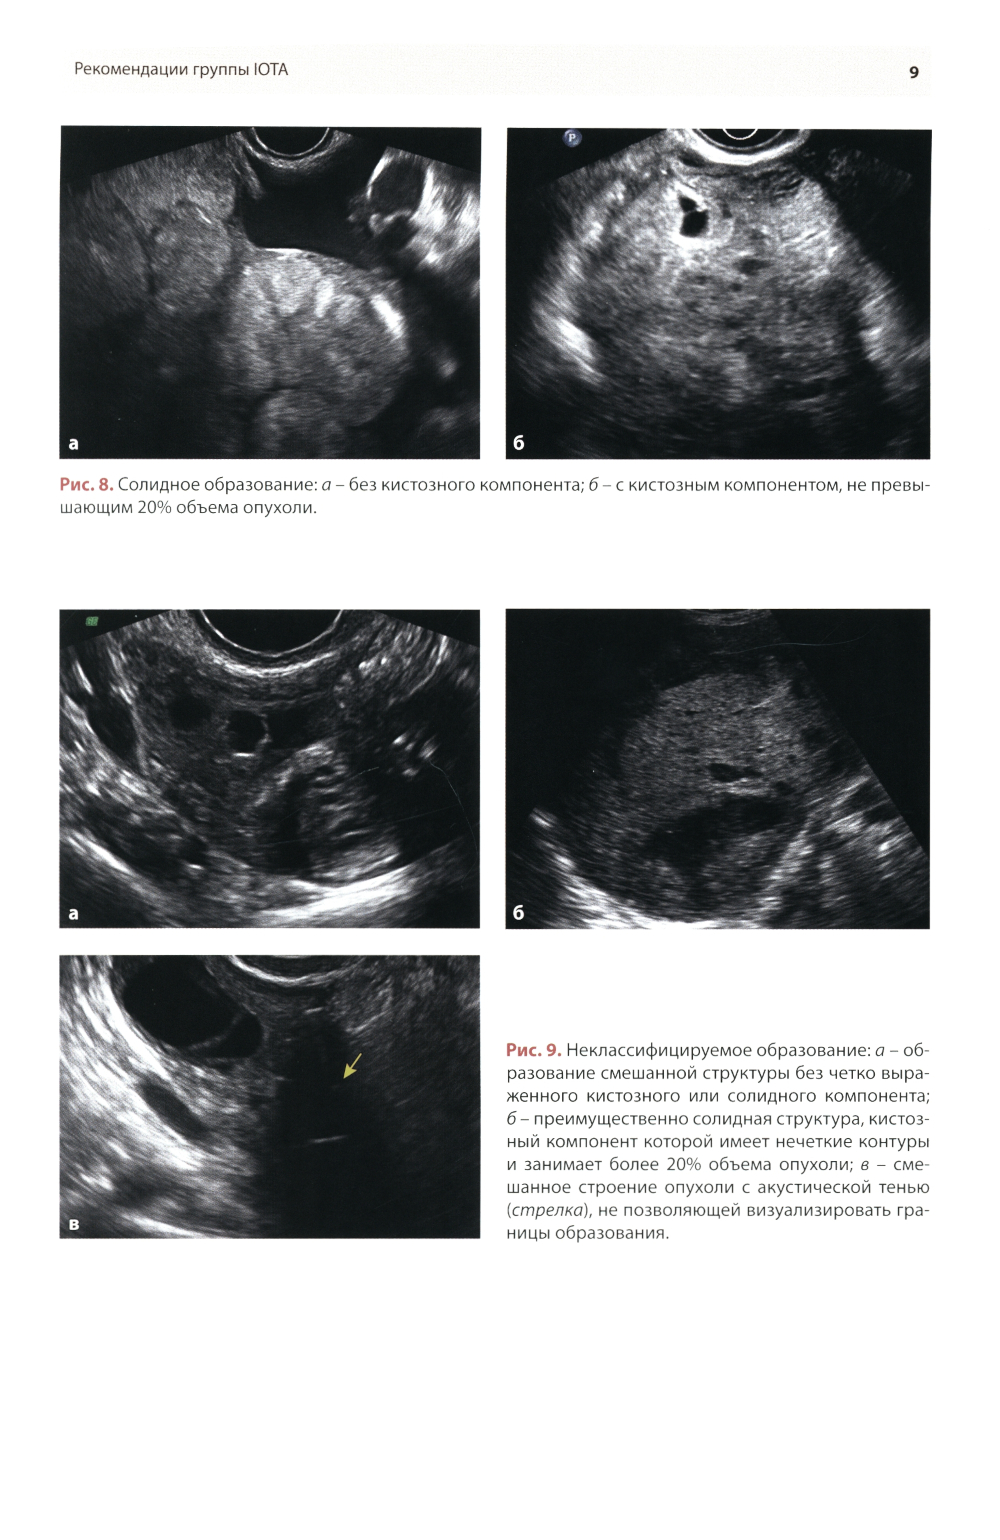

Методические рекомендации по стандартизации ультразвукового исследования с целью своевременной диагностики опухолевого процесса. Книга также включает вопросы дифференциальной диагностики физиологических изменений яичников, опухолевидных и опухолевых заболеваний и маршрутизации пациенток. Утверждено в качестве методических рекомендаций для проведения циклов первичной переподготовки врачей по ультразвуковой диагностике, тематического усовершенствования «Ультразвуковая диагностика в гинекологии», общего усовершенствования, ординаторов и аспирантов, проходящих обучение по направлению «Ультразвуковая диагностика, акушерство и гинекология».| Издательство | МЕДпресс-информ |